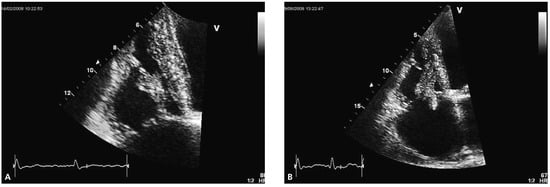

Transthoracic echocardiography revealed concentric left ventricular hypertrophy and a severely reduced global systolic left ventricular function (ejection fraction of 20–25%) due to inferior and posterior akinesia and substantial hypokinesia of the remaining wall segments. Both atria appeared dilated. The right ventricle was visually dilated with marked tricuspid annular dilation (50 mm) and functionally impaired (TAPSE 1.1 cm, TDI 10 cm/s). The aortic and mitral valves were remarkable for severe degenerative signs but besides a slight mitral regurgitation they were functionally normal. Attached to the septal leaflet of the tricuspid valve, an inhomogeneous structure partially prolapsing into the right atrium during systole was found (Figure 1A), associated with visually mild tricuspid valve regurgitation. The pressure gradient across the tricuspid valve was 65 mm Hg suggesting severely elevated systolic pulmonary arterial pressure. A CT scan of the chest confirmed pulmonary emboli in the right main pulmonary artery and in a segmental artery of the left upper lobe.

Figure 1.

(A) Transthoracic echocardiogram showing a right ventricular mass (apical four chamber view). (B,C) Magnetic resonance images demonstrating a right ventricular thrombus.